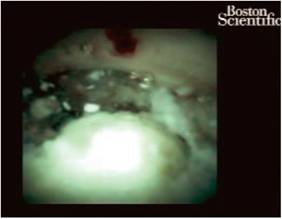

Para esto se realizó una CPRE con canulación selectiva de la vía pancreática y un pancreatograma, en el que se observó una dilatación sacular de 3 cm asociado con un cálculo de 15 mm en la cabeza del páncreas; se pasó una guía hidrofílica alojándola en el ducto pancreático y, posteriormente, se realizó una esfinterotomía pancreática. Se retiró el papilótomo, sobre la guía se montó el catéter del Spyglass, se logró acceder al conducto pancreático en el que se observó una gran dilatación y la presencia de un cálculo ovoide de aspecto blanquecino (Figura 2). Se pasó una sonda láser Holmium (Figura 3) y se fracturó el cálculo en múltiples fragmentos, se extrajo su totalidad con la canastilla y se dejó un stent de 7 f para garantizar el drenaje de residuos adicionales. Se mantuvo durante observación clínica por 24 horas, en las que tuvo una adecuada evolución. Durante los controles ambulatorios el paciente manifestó un adecuado control de síntomas, sin requerimiento de uso de analgésicos hasta la fecha debido a la resolución del dolor.